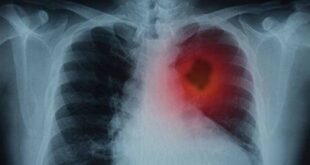

सिगरेट पीना स्वास्थ्य के लिए काफी खतरनाक होता है। सिगरेट पीने से होने वाले नुकसान के बारे में सभी को पता है। लेकिन अब इसके बारे में एक नई रिसर्च सामने आई है। इस रिसर्च में दावा किया गया है कि पूरे जीवन में सिर्फ 100 सिगरेट पीने से भी दिल की बीमारी और समय से पहले मौत का खतरा काफी बढ़ सकता है। अमेरिका के मैरीलैंड राज्य के बाल्टीमोर में स्थित जॉन्स हॉपकिंस यूनिवर्सिटी के वैज्ञानिकों ने इस पर रिसर्च की है।

जॉन्स हॉपकिंस यूनिवर्सिटी के वैज्ञानिकों ने 20 सालों तक 3 लाख से ज़्यादा वयस्कों की आदतों ओर रिसर्च की। उन्होंने पाया कि हर दिन सिर्फ दो सिगरेट पीने वाले पुरुषों और महिलाओं में मौत का खतरा 60% तक बढ़ जाता है। वहीं इन लोगों में दिल की बीमारी का खतरा भी 50% ज़्यादा होता है। सिगरेट पीने से स्ट्रोक का खतरा भी बढ़ जाता है।

रिसर्च में यह भी सामने आया कि सिर्फ सिगरेट कम कर देने से खतरा पूरी तरह खत्म नहीं होता। जो लोग स्मोकिंग छोड़ चुके हैं, उनमें भी 20 साल बाद तक दिल की बीमारी का खतरा बना रहता है।